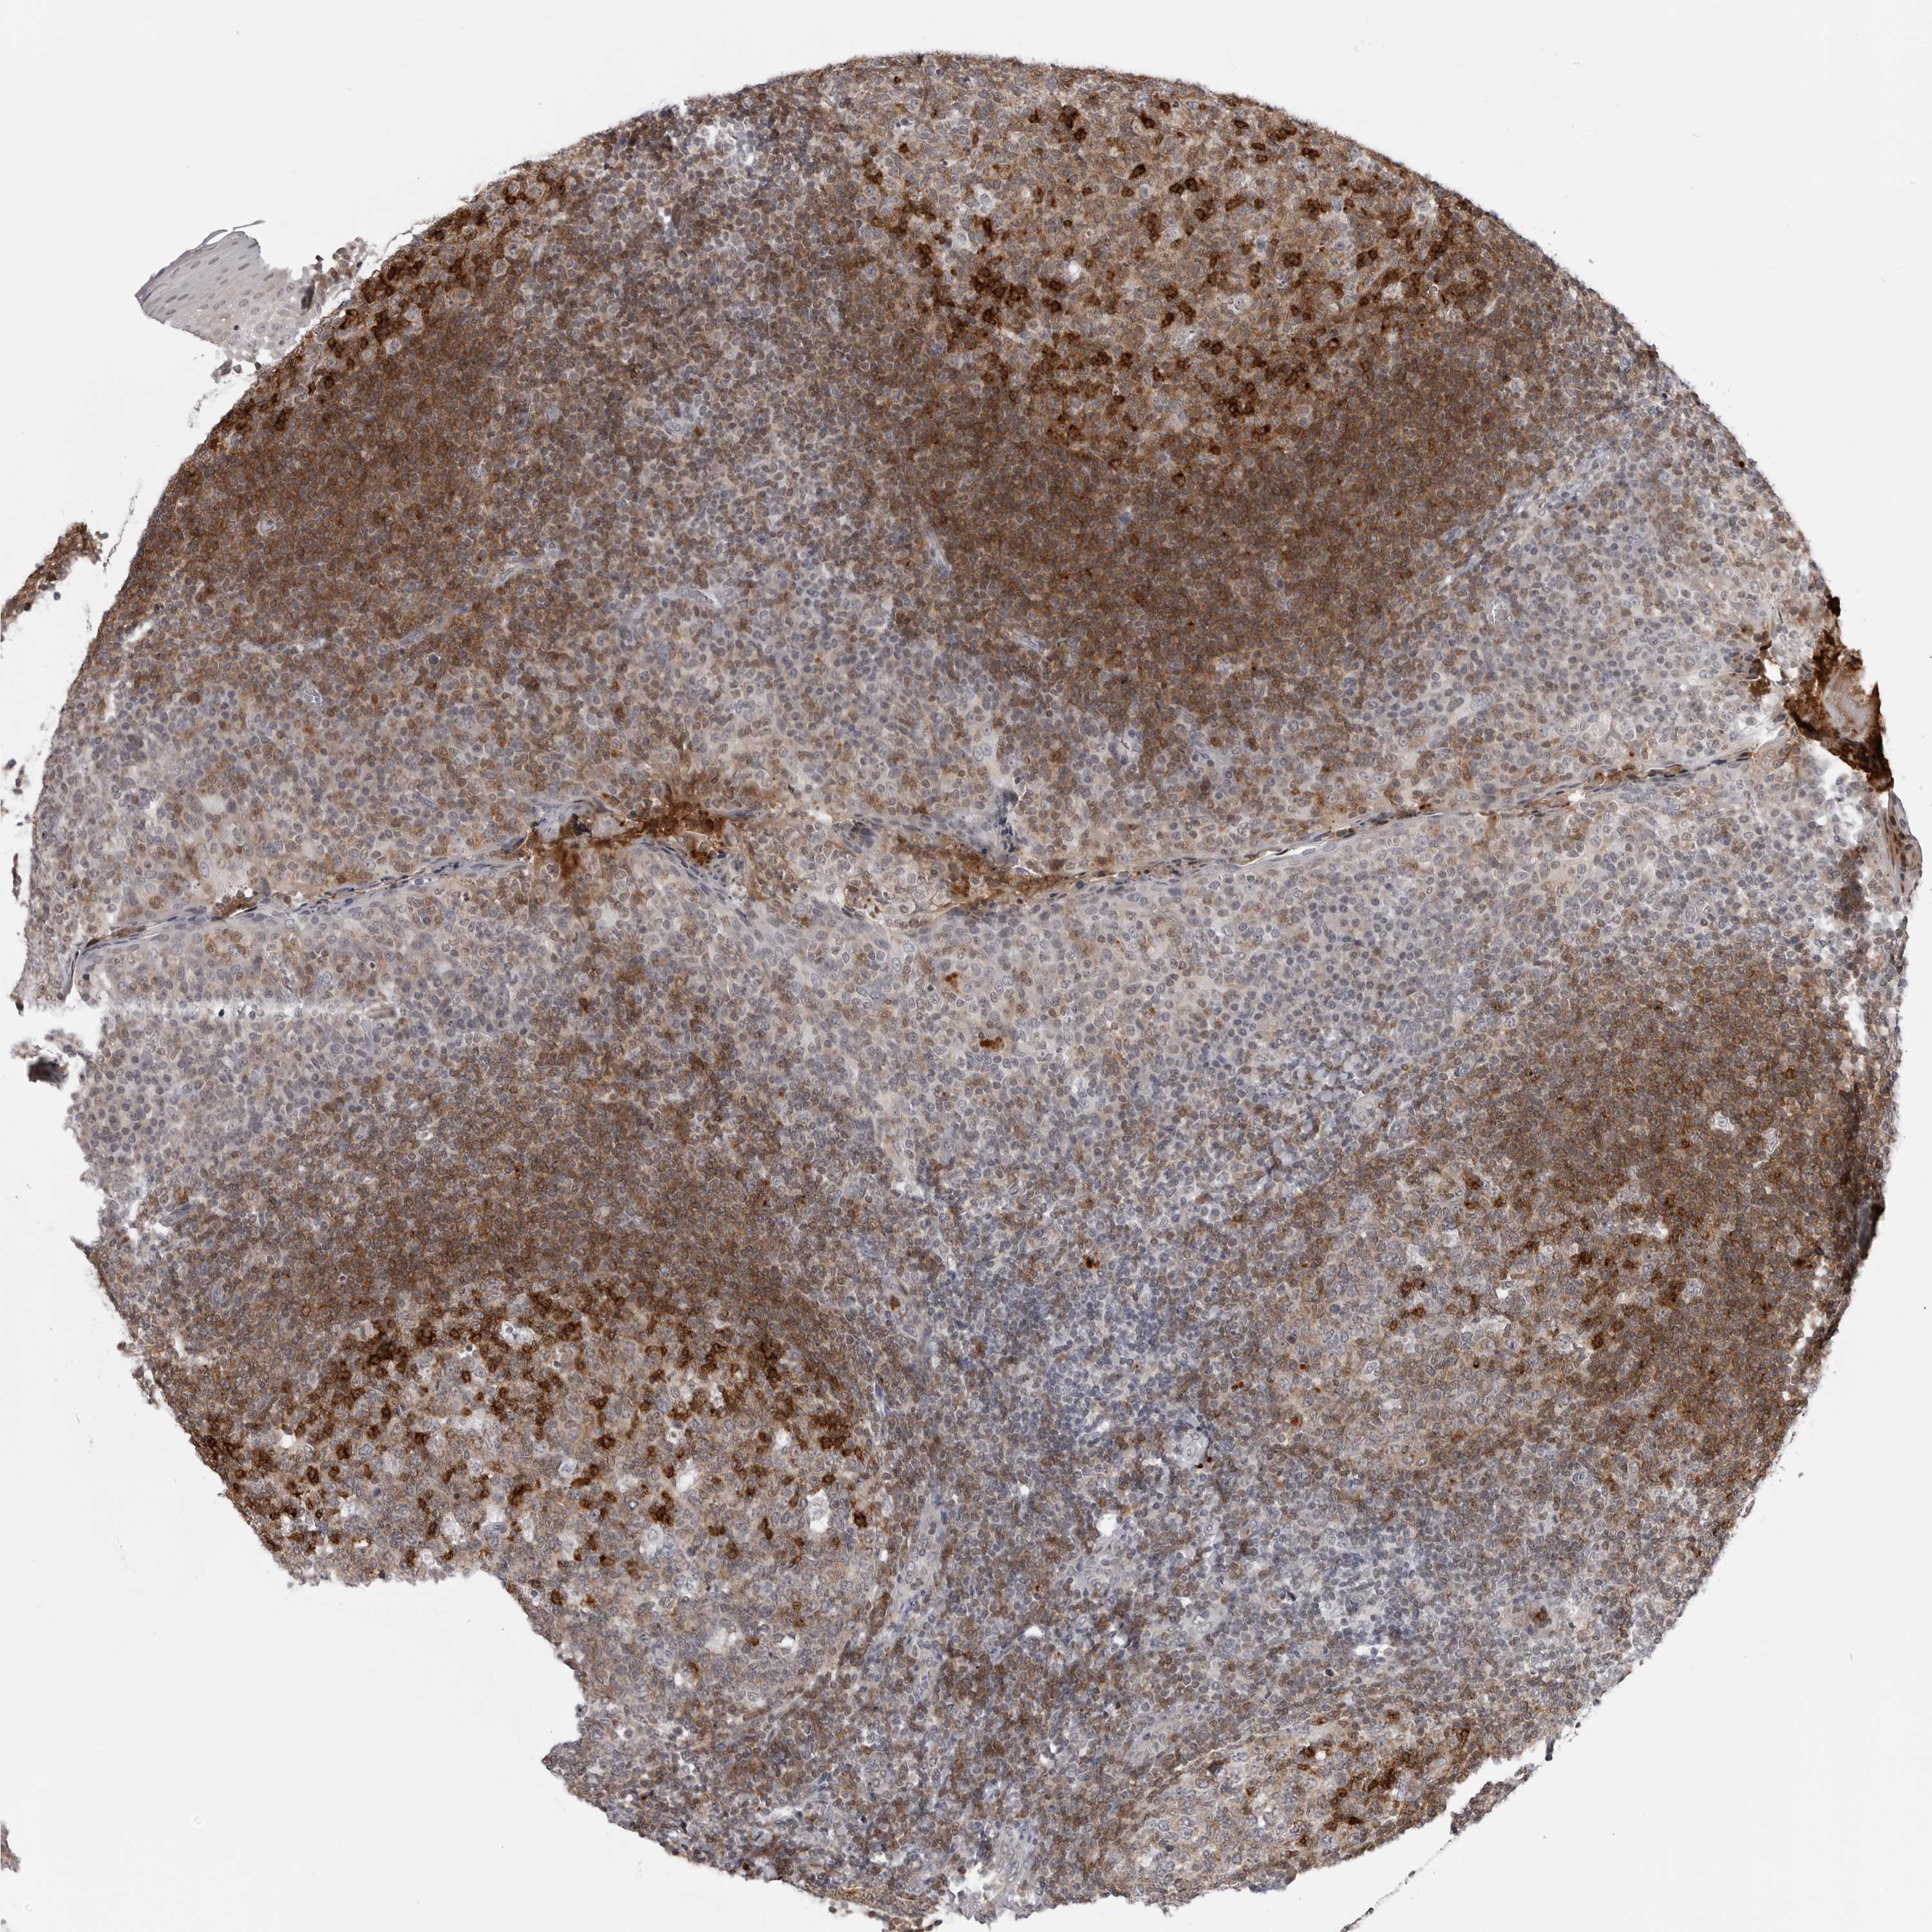

Tissue expression of CCR7 Staining in tonsil The Human Protein Atlas

Human Protein Atlas Tonsil we generated an atlas of the human tonsil composed of >556,000 cells profiled across five different data. we generated an atlas of the human tonsil composed of >556,000 cells profiled across five different data. we generated an atlas of the human tonsil composed of >556,000 cells profiled across five different data. the tonsils are a set of lymphoid organs consisting of large, partly encapsulated aggregations of lymphoid tissue facing. tonsils are part of our immune system and consist of large, partly encapsulated aggregations of lymphoid tissue. If you continue, we'll assume that you are happy to receive all cookies. we generated an atlas of the human tonsil composed of >556,000 cells profiled across five different data. the pathology section contains mrna and protein expression data from 17 different forms of human cancer. we use cookies to enhance the usability of our website.

From www.proteinatlas.org